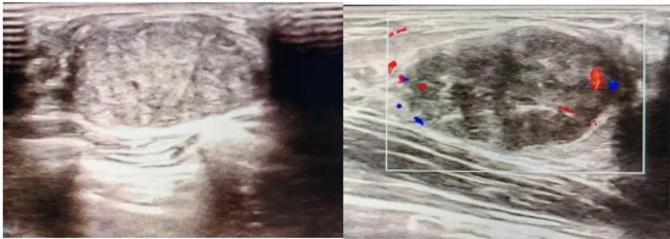

三、彩超檢查:無創(chuàng)檢查的“黃金眼”

高分辨率:可清晰顯示腫塊形態(tài)、血流信號,敏感度達(dá)80%-90%。

2.彩超報(bào)告關(guān)鍵指標(biāo)

形態(tài):良性多呈橢圓形或分葉狀,邊界光滑。

縱橫比: 良性通常<1(橫徑>縱徑) 。

血流信號:纖維瘤血流較少,惡性常伴豐富雜亂血流。

鈣化:粗大鈣化多為良性,細(xì)小簇狀鈣化需警惕惡性。

BI-RADS分級:2-3類提示良性,4類以上需進(jìn)一步檢查。

典型表現(xiàn):

橢圓形低回聲團(tuán)塊,包膜完整,內(nèi)部回聲均勻,后方回聲增強(qiáng),周邊無“蟹足樣”浸潤。